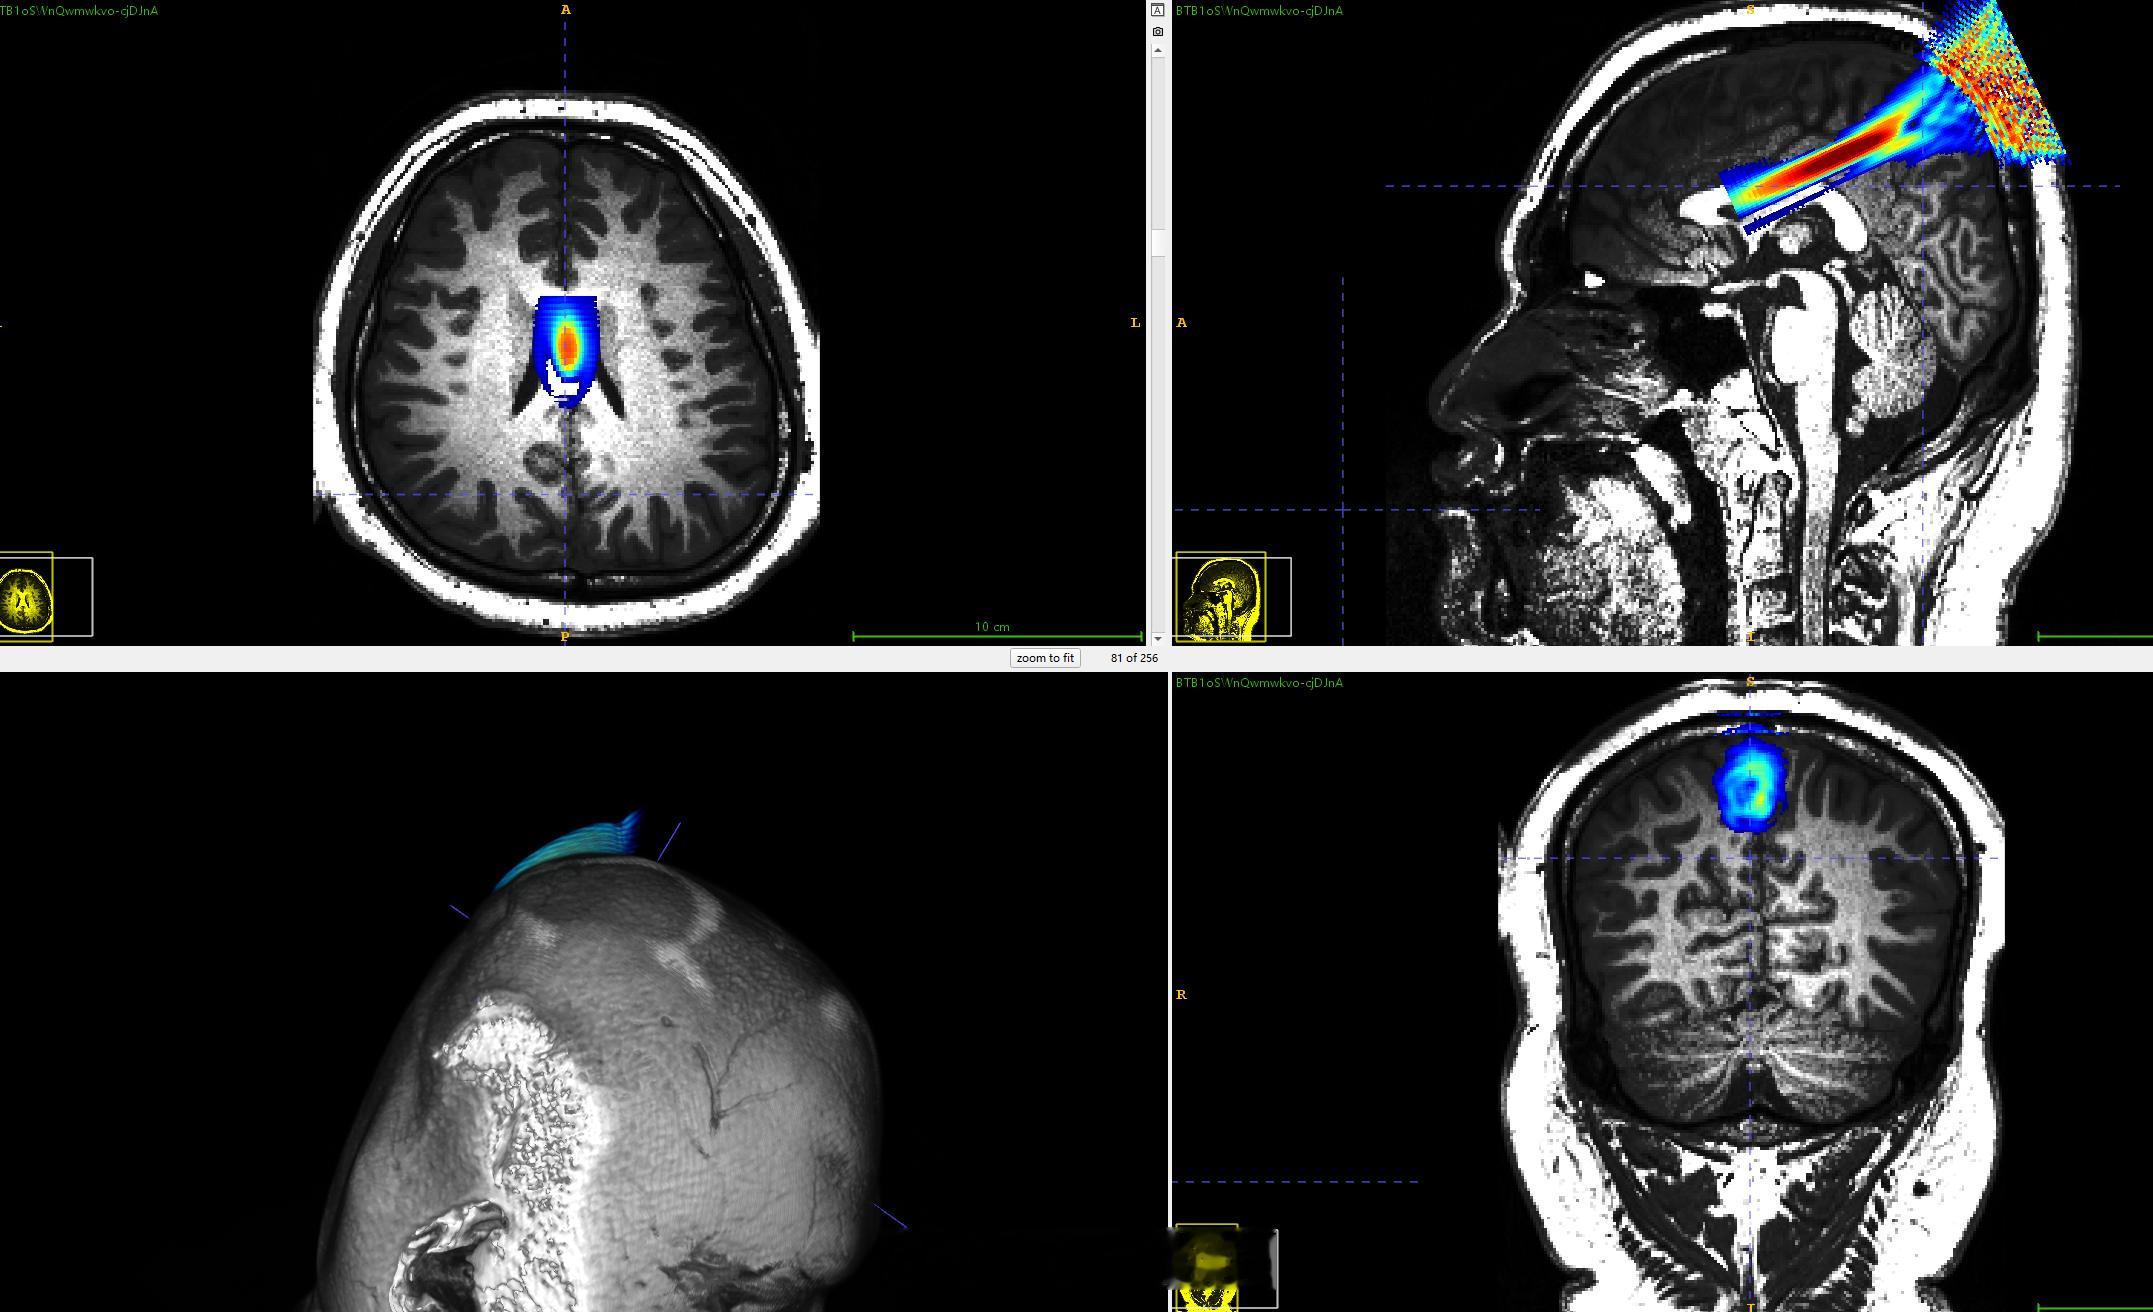

要把这个效果做出来,两个体数据渲染,其中一个场数据 渲染出像素伪彩、透明度

这是做什么工作的?电脑上也看不懂